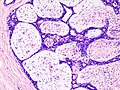

Tubular adenoma of the breast

- Considered by many a variant of fibroadenoma.

Features:[8]

- Well circumscribed lesion.

- Closely packed uniform tubules, lined by a single layer of epithelial cells and an attenuated myoepithelial cell layer.

- Stroma is generally more sparse than in conventional fibroadenoma